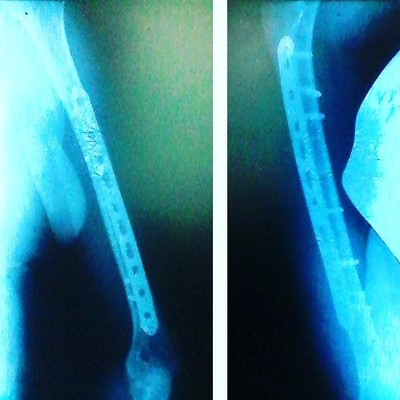

Ноги вскоре потеряли чувствительность и меня начали собирать обратно. Составлять вместе осколки костей и крепить их шурупами на титановую пластину. Одну кость на пластину, а вторую так состыковали - сказали, был риск нервы задеть.

Пластины надо снять примерно через год. Иначе металл немного разрушает кость и сам немного разрушается от динамических нагрузок. При этом он прирастает к кости все сильнее и за время пребывания в больнице я видел случаи, когда пластину снять не смогли. Поэтому надо снять. Две недели назад мне пластины сняли, так что нога снова разрезана от ступни до колена. Но поскольку кости целы - можно спокойно ходить на второй день, и даже обезболивание не требуется после первых суток. Вроде огромные разрез, а на фоне перелома почти никакого дискомфорта